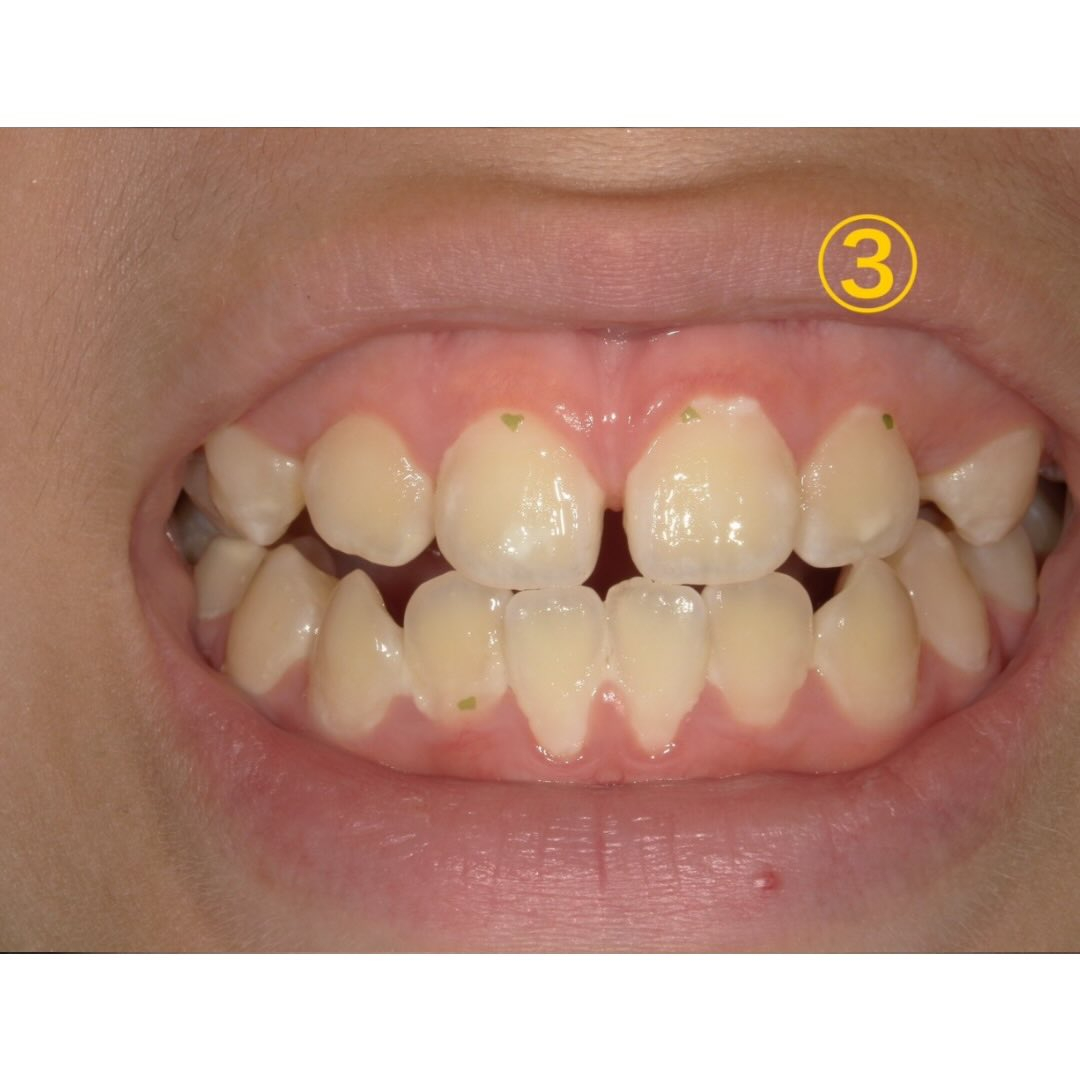

しかし、③の写真をご覧下さい。

汚れの量が一気に増えたのが分かります🔎

この時期から仕上げ磨きはせずに自分で歯磨きをするようになったそうです。

食べ物も着いていたので歯を磨いてるか確認した所、忙しくて磨いてない!との事でした🥲

この時は珍しくあまり治療に協力的では無く、染め出しも行えず、しっかり磨くことを伝え経過を見ることにしました👀